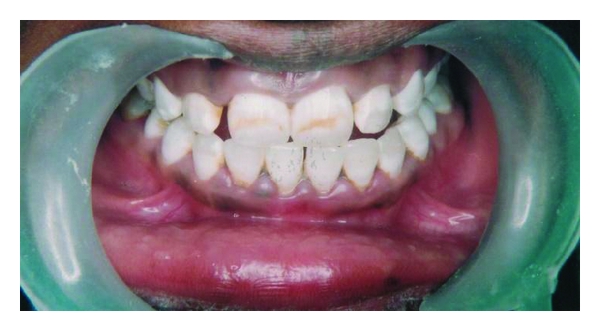

A twenty-five year-old-male patient came to the dental clinics for routine dental care. His chief complaint was to remove and/or minimize the noticeable brown/yellow staining of his teeth. He wanted the least invasive and most cost-effective treatment to change his smile. A review of his medical history and past dental history revealed no contraindications to dental treatment. In consideration of his age, the patient was not interested in treatment options that involved significant removal of tooth structure, such as porcelain or composite resin veneers. From the appearance of his teeth, a diagnosis of mild fluorosis staining determined by using Dean’s Fluorosis Index (Table 1) was sent on the anterior teeth in the aesthetic zone, with the most significant staining occurring on the maxillary anterior teeth, with light brown streaks in the middle third of the facial surfaces (Figure 1).